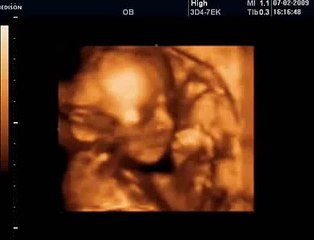

SAKARYA'DA yaşayan 24 yıllık evli Havva ve Mehmet Kesikbaş çifti, doğal yollardan çocuk sahibi olamayınca çeşitli tedavi yöntemlerine başvurdu. br 4 tüp bebek denemesi başarısız sonuçlanan çiftin bebek özlemi, erken menopozda öncelikli kullanılan PRP yöntemi ile son buldu. 6 haftalık hamile olan Havva Kesikbaş, bebeğini kucağına alacağı günü bekliyor.brSakarya'da yaşayan Havva (42) ve Mehmet Kesikbaş (44) çifti, 24 yıl önce dünya evine girdi. Çift, doğal yollarla çocuk sahibi olamayınca tedavi yöntemlerini araştırmaya başladı. Sakarya ve İstanbul arasında mekik dokuyan Kesikbaş çifti, çeşitli hastanelerde 4 kez tüp bebek tedavisi oldu. Zaman zaman umutlarını yitiren çiftin bebek hasreti 24 yıl sonra son buldu. Kadın Doğum Uzmanı Prof. Dr. Birol Vural tarafından uygulanan 'Yenileme ve Gençleştirme' özelliği olan PRP Yöntemi sonrası Havva Kesikbaş'ın gebeliği gerçekleşti.